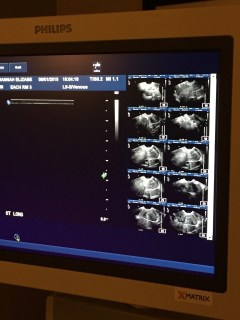

This summer wound down with our minds refocused on the legwork of adoption. We started drawing up plans and timelines and praying for the fatherless that we hope will someday be part of our quiver-full. Imagine our surprise then, when against all the odds that had been given us, we were staring at the very realness of another little one… of our own

The only communication I could have with Mark was by text that day; he couldn’t escape his class, and for the second time, I sat alone in a cold room staring at a dark ultrasound, void of the flicker of life. While I waited to be taken back to my room, they sat me in a hallway outside the ultrasound rooms. I sat in paralyzed agony, watching woman after woman stroll to the exam rooms, plump, ripe, life-bellies cupped beneath pregnant hands. I bitterly scowled inside, already hurling the questions that I knew I probably wouldn’t get answers to on this side of eternity.